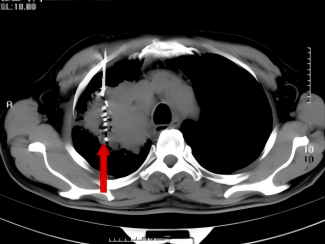

2011年,一名70岁患者因出现咳嗽、咳痰带血等症状就诊于我院呼吸门诊,在完善CT等相关检查后,患者被诊断为右上腺癌(多原发),在充分的与患者及家属进行沟通后,明确表示不接受外科手术,科室为患者制定并实施了CT引导下经皮肺穿刺射频消融+碘125粒子植入放疗+化疗的治疗方案。

术 前

术 后

患者分别在治疗4月和1年后复查胸部CT显示病灶稳定,病情得到进一步控制。

术后4月复查